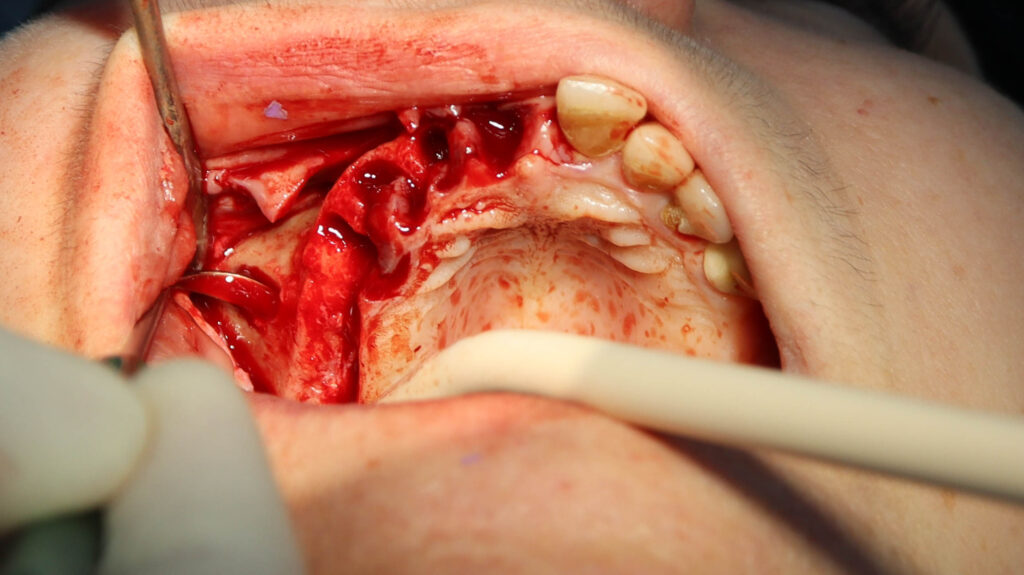

процесс работы

Что было сделано:

На верхней челюсти были удалены зубы, которые находились в неудовлетворительном состоянии, проведена комплексная имплантация по системе All-on-6, установлены 4 имплантата Megagen AnyOne и 2 скуловых имплантата NeoDent.

процесс имплантации